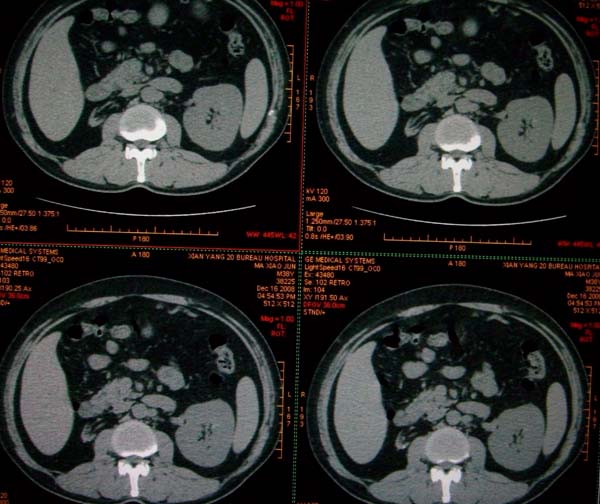

标题: CT17174:M38Y,体检超声提示右肾发育不良,病人无明显不适 [打印本页]

标题: CT17174:M38Y,体检超声提示右肾发育不良,病人无明显不适

右肾发育不良;考虑左肾下极血管平滑肌脂肪瘤可能,建议增强。

右肾微小发育不良  左肾下极错构可能

1)左肾下极占位性病变,不排除肾癌可能;建议行进一步检查。2)右肾发育不良。

左肾下极占位性病变,不排除肾癌可能;建议增强及明确内部组织ct值。右肾发育不良。

右肾发育不良。左肾代偿。左肾下极占位,性质待定,建议强化。

右肾发育不良。左肾下极囊实性占位,建议增强。